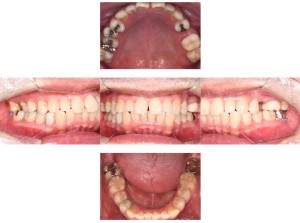

インプラント治療の症例3

レントゲン写真

- Befor

- After

口腔内写真

| 年齢 | 50代・男性 |

|---|---|

| 主訴 | 左下7番 |

| 治療内容 | 右下7番インプラント埋入 |

| 治療費 | 合計:572,000円 診断料:55,000円 埋入料:165,000円 サージカルガイド:55,000円 静脈内鎮静麻酔:77,000円 仮歯:55,000円 上部構造(フルジルコニア):165,000円 (2023年1月現在) |

| 治療期間 | 約8ヶ月 |

| リスク・副作用 | リスク・副作用 |

| 治療方針 | 骨が十分にあるため、骨造成をすることなく埋入した。かみ合わせが強いので、負荷がかからないよう、夜寝るときにマウスピースをつけるよう指示をした。 |

| 担当者所見 | 左下6番7番のインプラントは他院で埋入しており、右下7番は抜歯したままで、かみ合わせの歯が落ちてきてしまうのでインプラントを埋入しました。 |